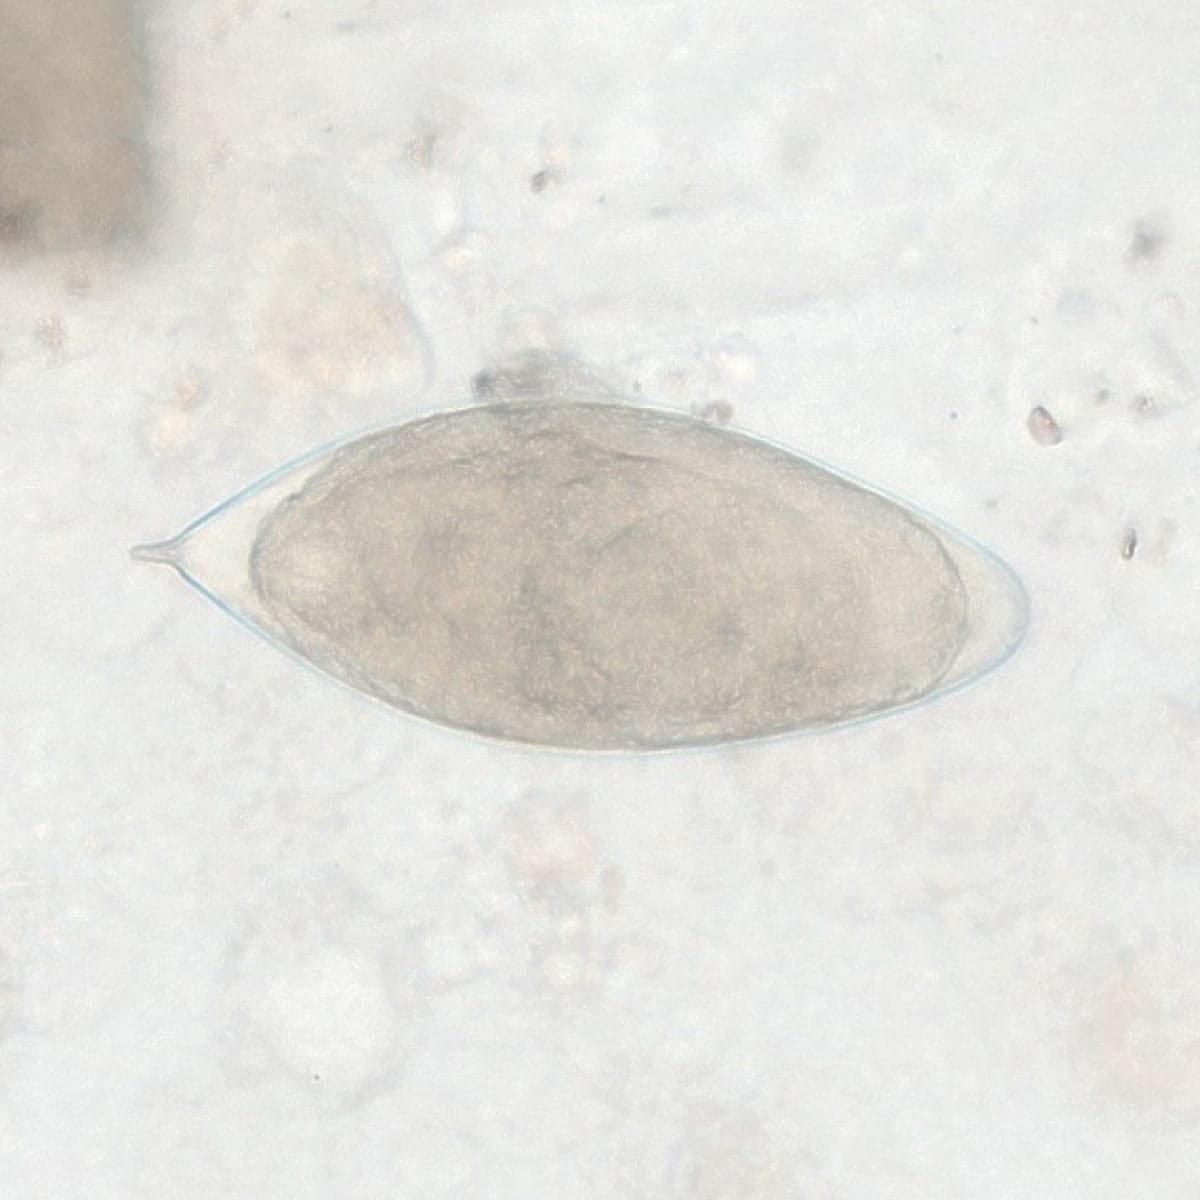

Automatic detection of rare species

Built on worldwide parasite-positive specimens, ParaScout AI identifies a vast number of parasite species, including those that are clinically rare or challenging to find.

Once the data is uploaded, the AI instantly identifies parasite species. You receive visual evidence for every finding, with dimensions to confirm the identification. Simply review the AI’s results and provide the final diagnostic confirmation.